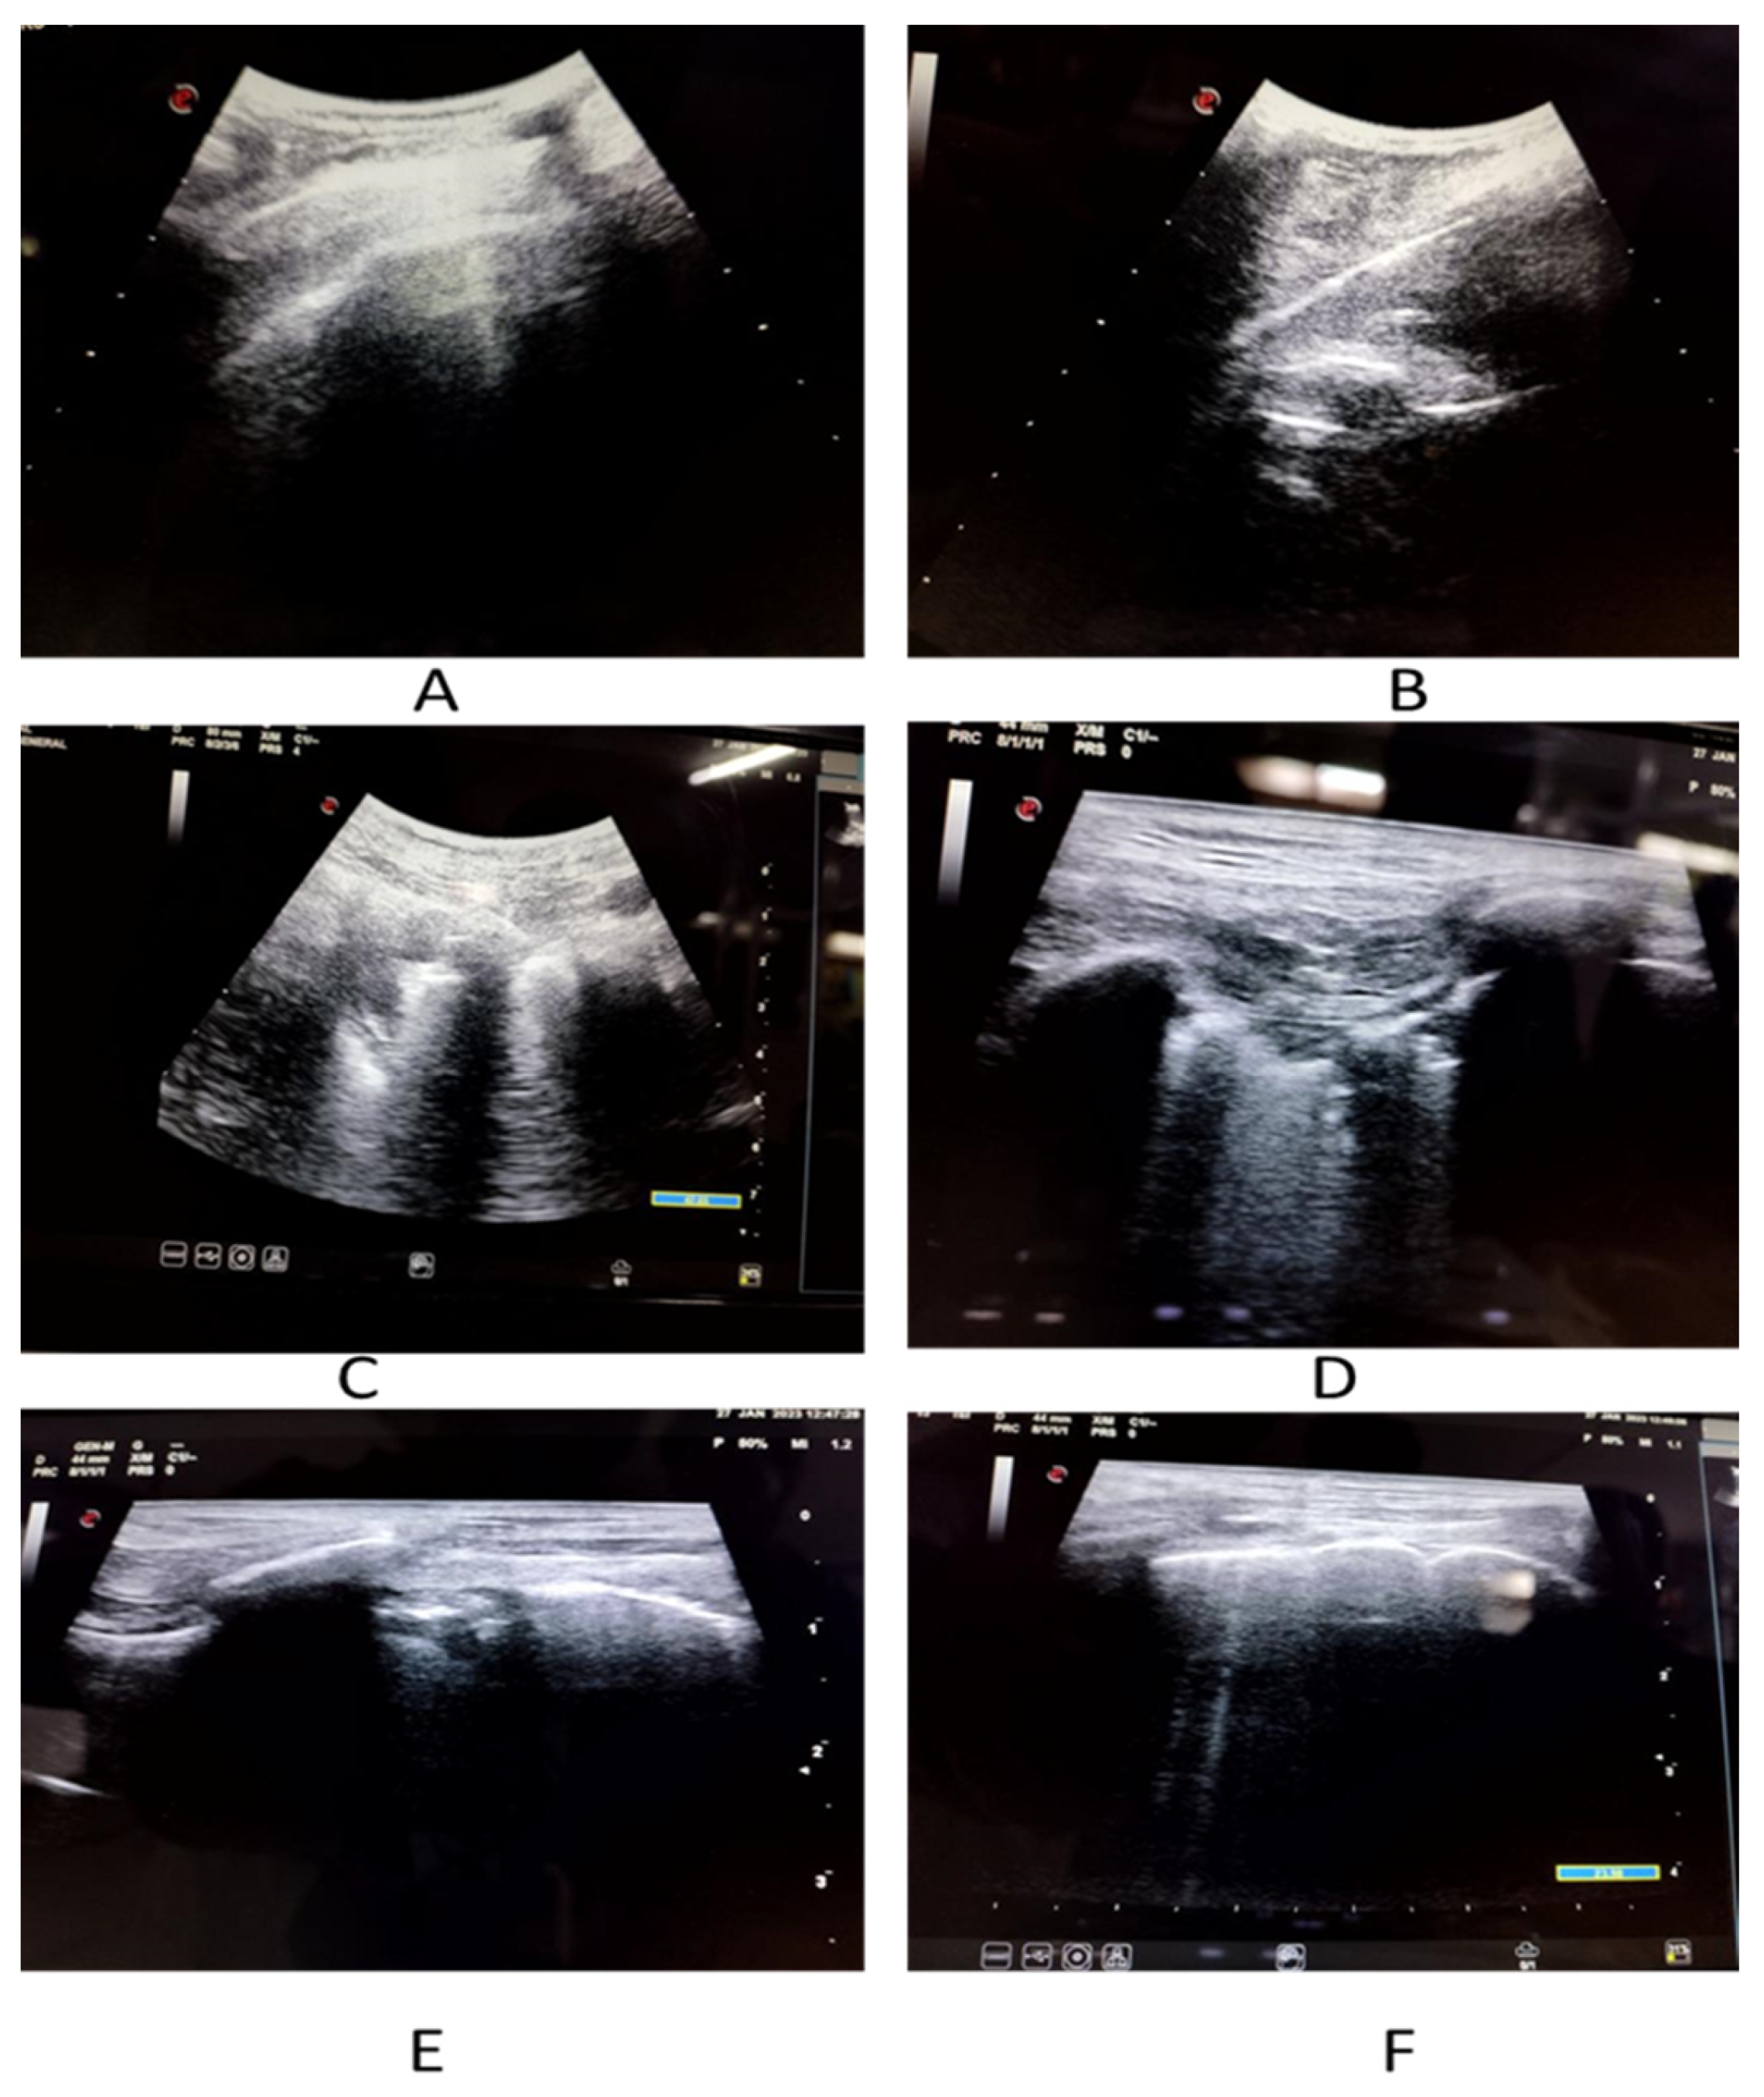

2.2. Ultrasound Data Collection

An experienced sonologist who had knowledge of performing and elucidating LUS performed all the examinations. The LUS exam was carried out in accordance with a 12-zone protocol. Careful evaluation was done to look for pleural effusions, confluent B-lines (CBL), isolated B-lines (IBL), irregular pleural line (IPL) and consolidations (Figure 2 and Figure 3). Both halves of the chest were scanned on their anterior, lateral and posterior aspects. These 12 zones were evaluated for the isolated B-lines (1 point), confluent B-lines (2 points) and consolidations or pleural effusion (3 points) with score range from (0–3). By summing the scores of all 12 zones the total lung score was achieved (range of possible scores: 0–36).

Figure 2.

Imaging spectrum of COVID-19 patients on LUS. (A) Shows thickened pleura with small pleural effusion. (B) Depicts thickened irregular pleural line. (C) Demonstrates confluent B-lines. (D) Reveals isolated as well as confluent B-lines. (E) Displays thickened irregular pleural line with confluent B-lines. (F) Denotes isolated B-lines.

Pattern of B-lines, either solitary and/or confluent, an uneven pleural line, and subpleural consolidations are all regarded as imaging signs of a compatible LUS exam. LUS examinations were performed using a GE Logic p5 USG machine, using a curvilinear array transducer and lung/cardiac pre-set. The sonologist performing the scan was blinded to all clinical details and HRCT findings.